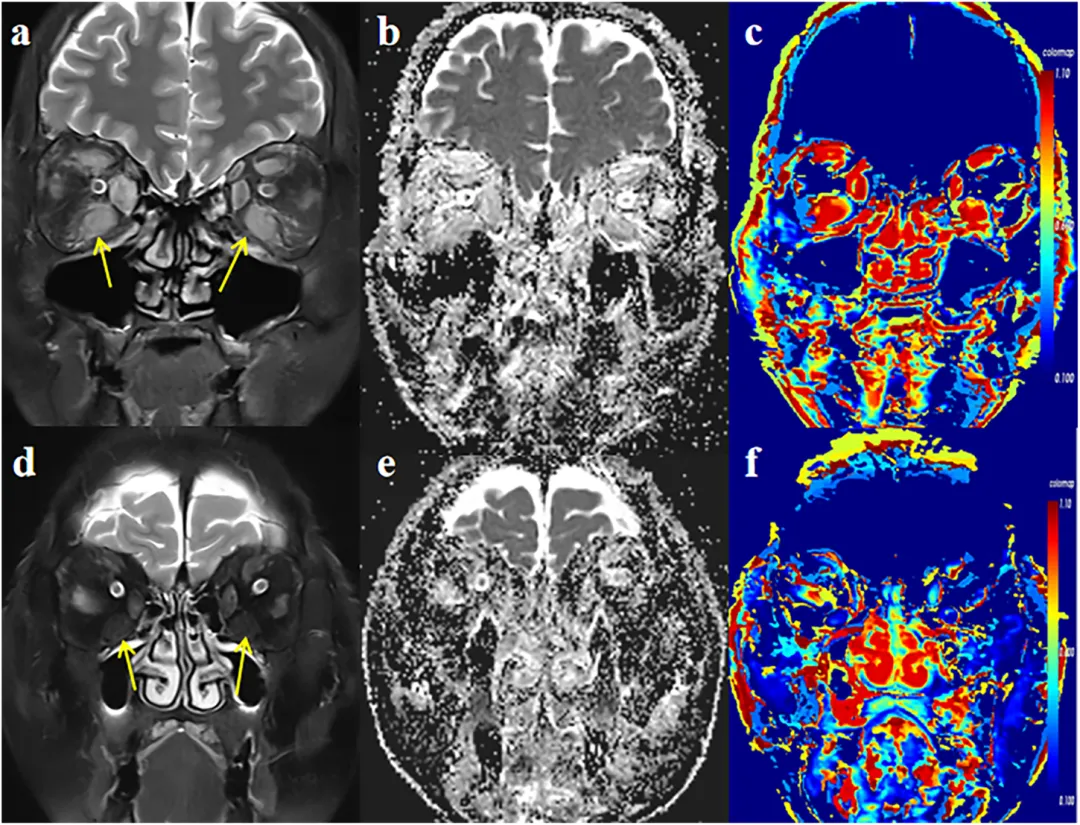

图2:影像分析示意图。展示眼外肌ROI勾画及参数提取过程。

图3:活动与非活动TAO患者的代表性影像图例。